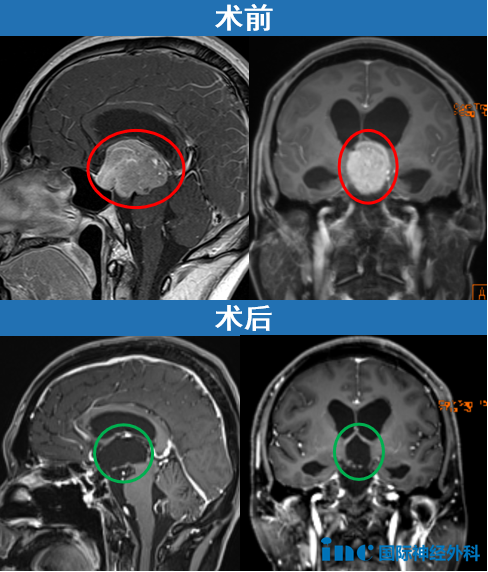

一位62歲女性患者,與垂體瘤抗?fàn)庨L達(dá)35年,曾因垂體瘤復(fù)發(fā)接受放射治療。此次因出現(xiàn)復(fù)視癥狀隨訪,發(fā)現(xiàn)已經(jīng)發(fā)展巨大的垂體瘤。

進(jìn)行開顱手術(shù),術(shù)后影像片子顯示腫瘤切除干凈。